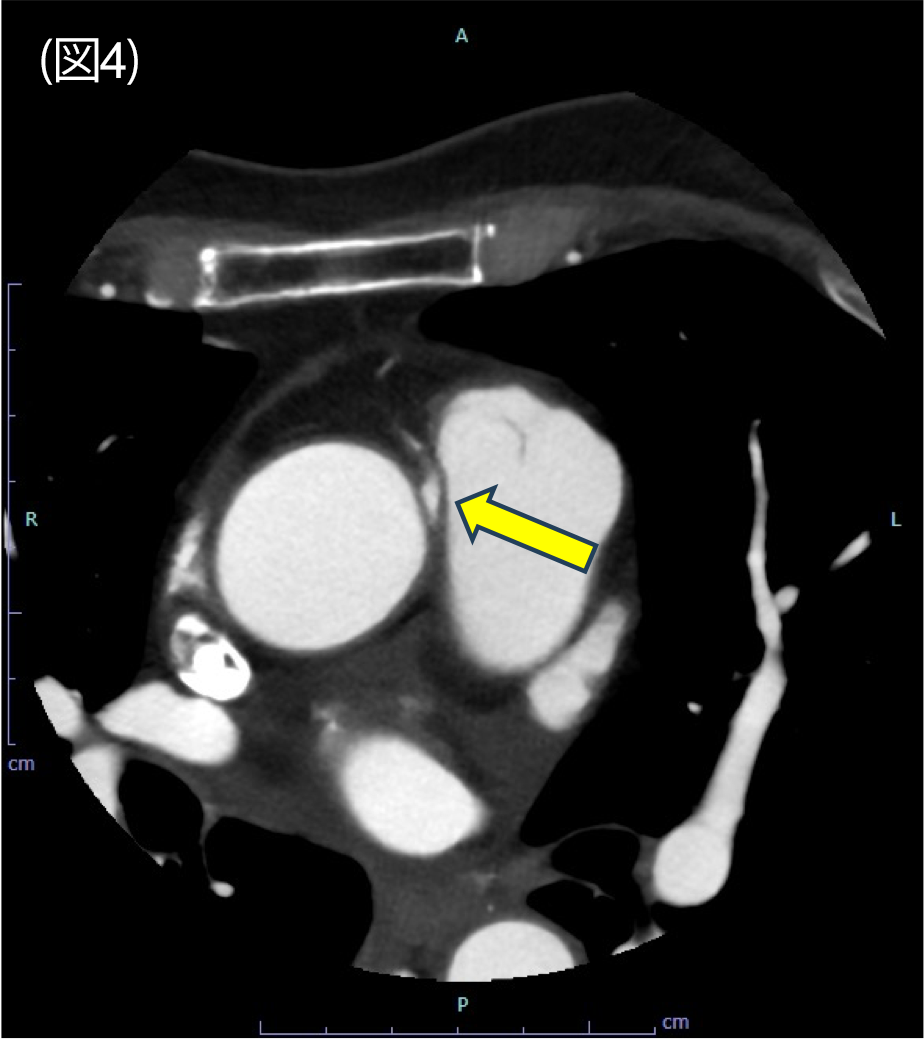

図4.冠動脈CT axial 像

右冠動脈は大動脈と肺動脈の間を走行している。